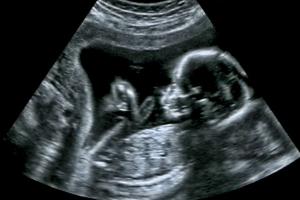

New study shows differences between male and female brains in utero

A new scientific study has found significant differences in the ways that the brains of male and female fetuses function prior to birth.

Washington D.C., (CNA) - Researchers conducted MRI scans on human fetuses in the womb, studying the functional connectivity (FC), or the neurological connections between different areas of the brain, for both males and females. They found connections between parts of the female brains that were almost nonexistent in the male brains.

"The present study demonstrates for the first time that development of fetal brain FC varies with sex," the researchers wrote, concluding that the fetal brain networks they observed likely lay the "building blocks" for brain development throughout rest of the baby's life.